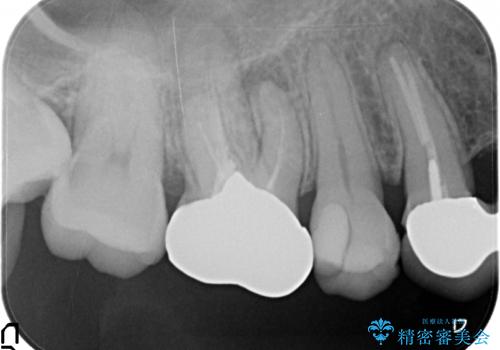

- 右上の奥歯でものを咬むと痛むため他院を受診したが、治療は難しいと言われたため当院にいらっしゃった方の症例です。

再根管治療を行い症状の緩解を確認後、オールセラミッククラウンによる補綴を行いました。